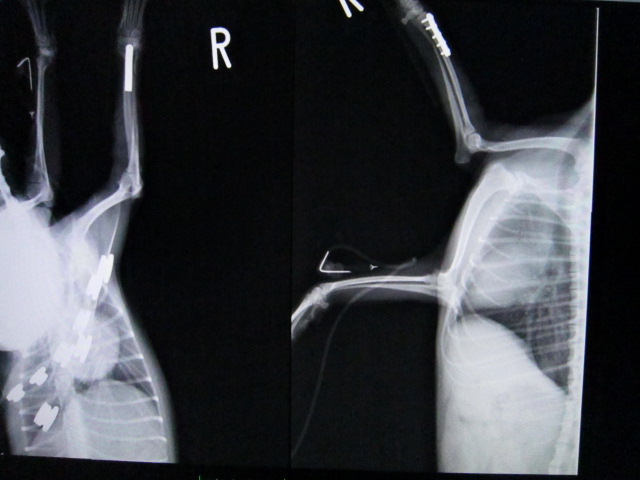

1週間外固定で様子を見たが悪化したため、手術によりプレート固定を行った。